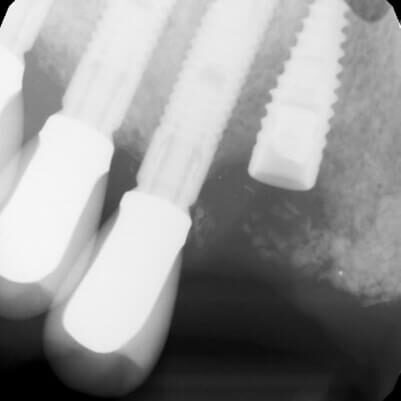

ULTRASONICS: Complications of Abutment Screw Retrieval Secondary to Prior Ultrasonic Attempts

There has been much written on the use of ultrasonics in retrieving fractured screw fragments, which I didn’t think a lot about until May of 2023, as it has not been a part of my fractured screw retrieval algorithm.